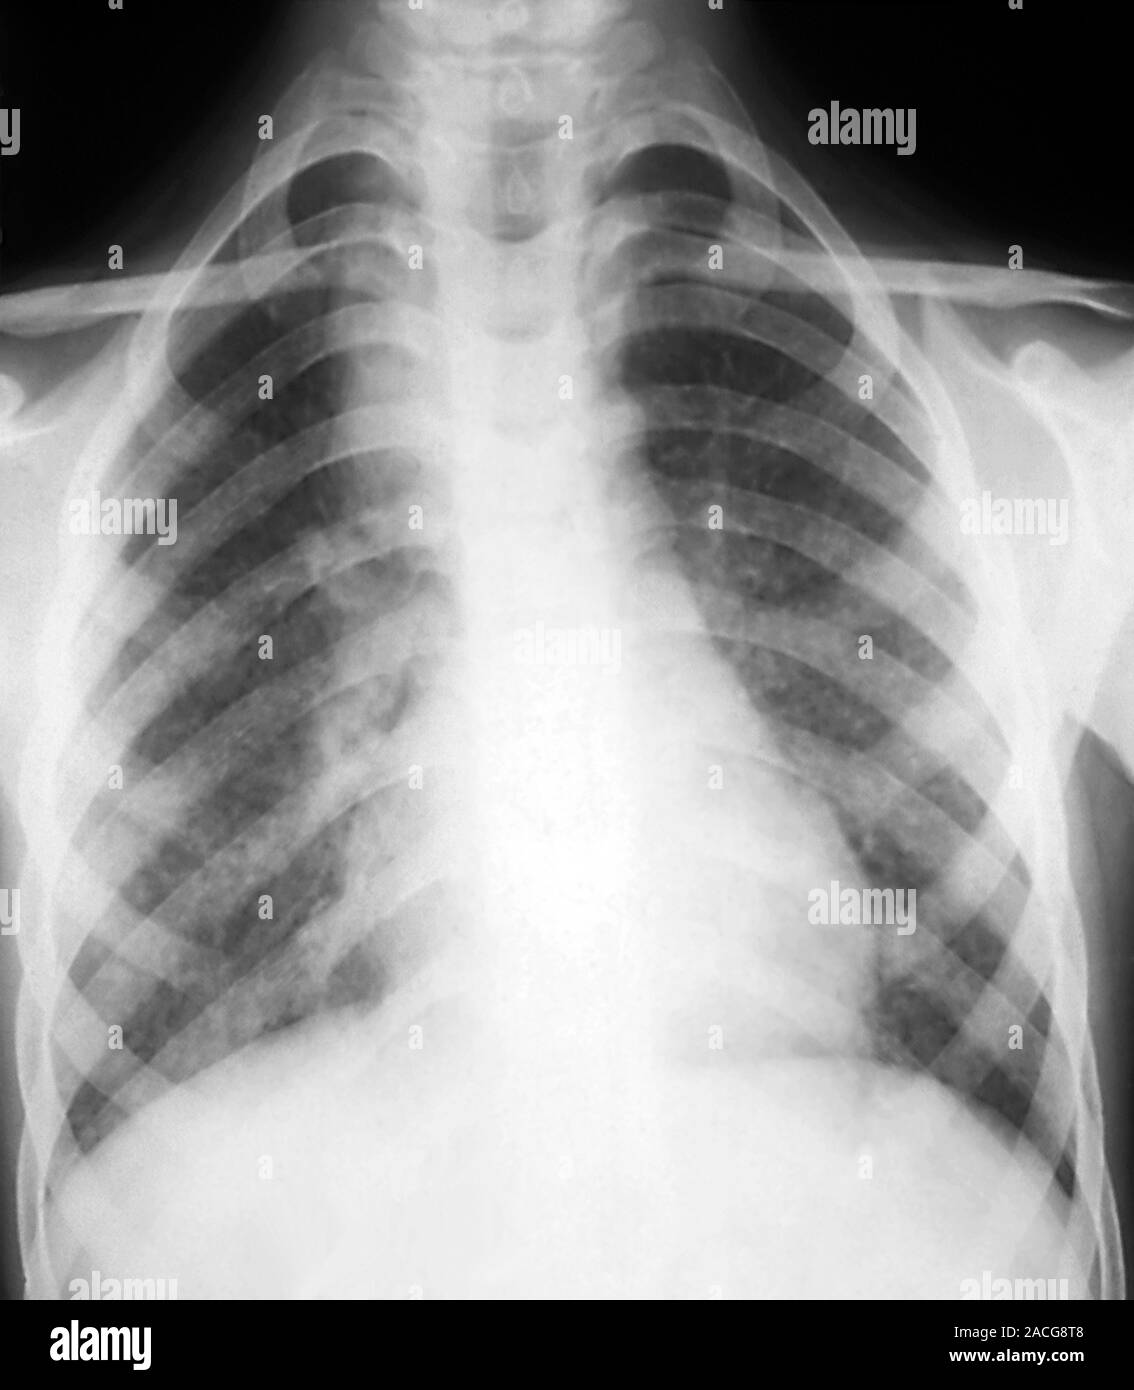

Xray of the chest of a patient, showing enlarged lymph nodes (at Can Chest X Ray Detect Enlarged Lymph Nodes There are many causes of enlarged lymph nodes in the chest. Generally, mediastinal lymphadenopathy is diagnosed with imaging tests, such as chest ultrasound, chest computed tomography (ct), positron emission tomography. The short answer, no, not always. While some cancers such as lung. This test isn’t needed if a ct of the chest is done. These can be cancerous, enlarged lymph. Can Chest X Ray Detect Enlarged Lymph Nodes.